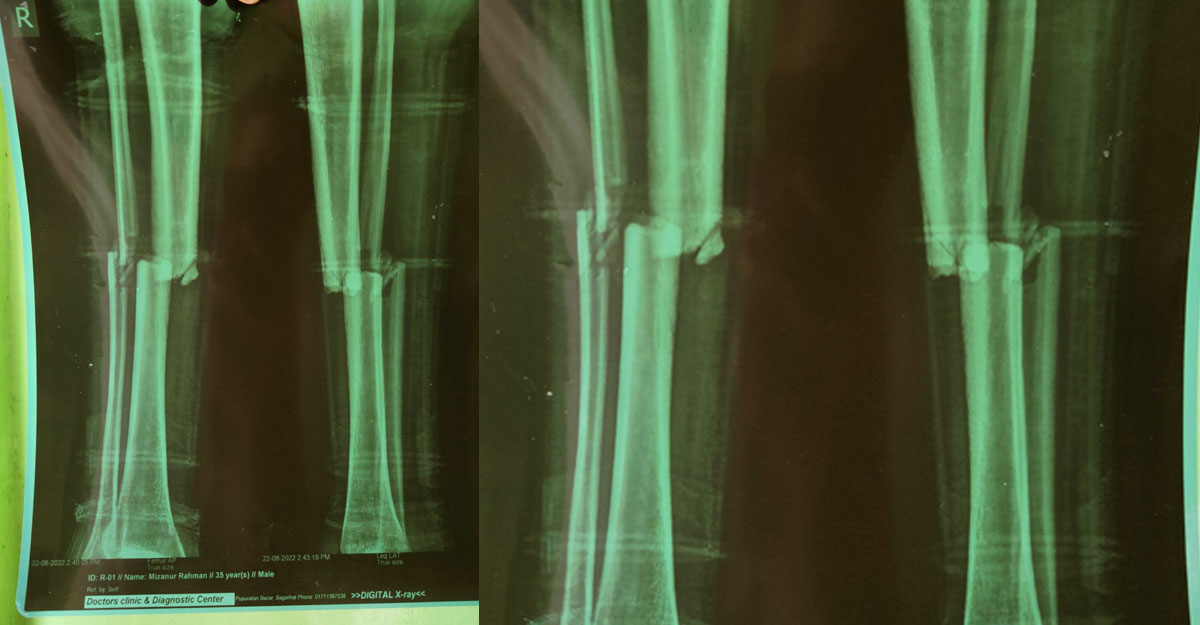

মিলন সেখ। বয়স ২৮ ছুঁই ছুঁই। পেশায় ট্রাকচালক। তিনি পিরোজপুর শহরের আলামকাঠী এলাকার বাসিন্দা। কয়েকদিন আগে চট্টগ্রামের সীতাকুন্ড এলাকায় সড়ক দুর্ঘটনায় তার দুই পায়ের হাড় ভেঙে যায়। চট্টগ্রাম থেকে উন্নত চিকিৎসার জন্য ঢাকায় নেওয়া হয় তাকে। সেখান থেকে চিকিৎসক পরিচয় দিয়ে মনিরুজ্জামান নামে এক ব্যক্তি তাকে বাগেরহাটে নিয়ে আসেন। তার অপচিকিৎসায় ট্রাকচালক মিলন এখন প্রায় পঙ্গু। মনিরুজ্জামান চিকিৎসার নামে লক্ষাধিক টাকা হাতিয়ে নিয়ে হয়েছেন লাপাত্তা।

ভুক্তভোগী মিলনের ভাই রাজু সেখ জানান, গত ২৩ জুন চট্টগ্রামের সীতাকুণ্ডে ট্রাক দুর্ঘটনায় দুই পায়ের হাড় ভেঙে আহত হওয়ার পর মিলনকে চট্টগ্রাম মেডিকেল কলেজ হাসপাতালে ভর্তি করা হয়। পরদিন তাকে উন্নত চিকিৎসার জন্য ঢাকায় পঙ্গু হাসপাতালে পাঠানো হয়। সেখান থেকে বলা হয় ১০-১৫ দিন পর অপারেশন করা হবে। পরবর্তীতে সেখানেই পরিচয় হয় মনিরুজ্জামান নামে এক ব্যক্তির সঙ্গে। তিনি তাদের অল্প খরচে পা ভালো করে দেওয়ার আশ্বাস দিয়ে প্রথমে এক মাস নারায়ণগঞ্জে রেখে চিকিৎসা দেন। পরে বাগেরহাটে নিয়ে আসেন। তিনি ৫০ হাজার টাকা নগদ ও বিভিন্ন সময়ে চিকিৎসার কথা বলে লক্ষাধিক টাকা হাতিয়ে নিয়েছেন।